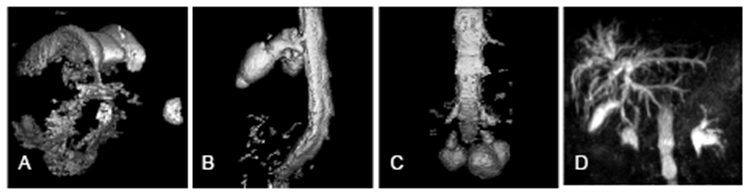

Контрастное усиление состоит в получении одного 3D-объема данных через определенное время после введения КВ. Часто при этом еще создается полностью аналогичный объем до введения КВ и применяется методика цифрового вычитания (субтракция) для улучшения контраста.

Динамическое контрастное усиление состоит в получении серии одинаковых 3D-объемов через определенный интервал времени, что позволяет анализировать динамику изменения сигнала в зоне интереса и строить динамические кривые. Именно это позволяет оценить наличие и степень выраженности патологии. Например, для злокачественных опухолей характерно быстрое накопление и быстрое вымывание КВ.

Количество таких объемов в серии может достигать нескольких десятков, а то и сотен. Поэтому для этого типа исследований используются сверхбыстрые ИП (обычно класса градиентного эха) и данные собираются в трехмерном К-пространстве.

Для DS-задач этот тип исследования представляет особую сложность именно из-за структуры данных. Во-первых, гораздо больше вариабельных параметров – не только тип КВ, но и количество 3D-объемов, интервалы между их измерениями и т.п. Во-вторых, основная полезная для диагностики информация содержится в четвертом измерении – в динамике изменения сигнала одной и той же области. Извлечь эту информацию и представить в виде, пригодном для использования нейронными сетями совместно с другими сериями – нетривиальная задача.